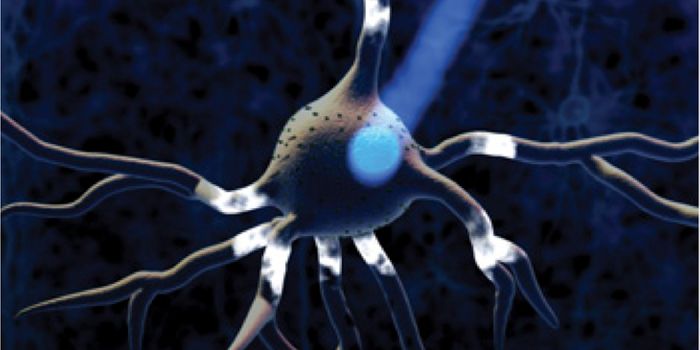

JUL 27, 2016NeuroscienceSynapses are the connections between neurons that allow them to communicate with each other. When synapses become compro ...

MAR 08, 2016ImmunologyScientists have grown tiny, barely visible “mini-brains.” These balls of neurons and other human cells mimic ...

NOV 18, 2015Clinical & Molecular DXThe human brain may not look like much, composed of about three pounds of soft mushy matter. But we all know that our br ...